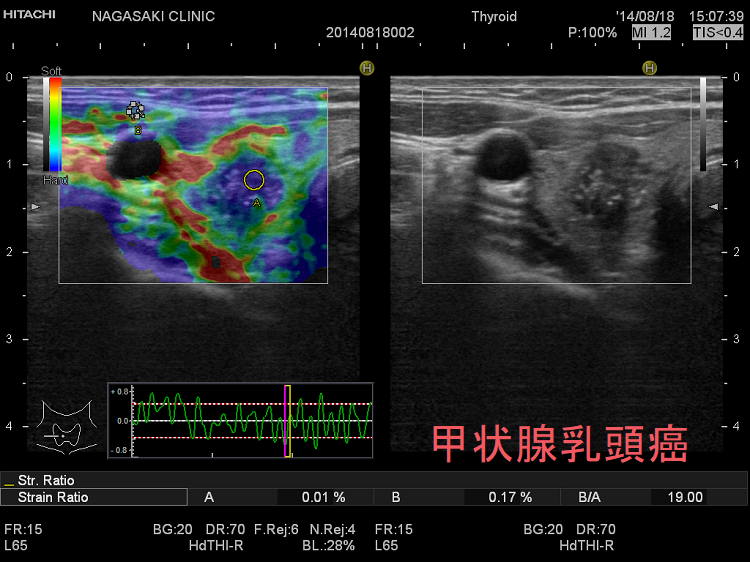

甲状腺乳頭癌濾胞癌は特徴的なパターンで青くなります。

エラストグラフィー甲状腺濾胞癌良性濾胞腺腫と鑑別する判断材料になります。甲状腺濾胞癌は、穿刺細胞診で診断がほぼ不可能です(良性濾胞腺腫腺腫様結節と同じくクラス3にしかなりません)。甲状腺超音波(エコー)検査でも良性濾胞腺腫と鑑別するのは非常に困難ですが、甲状腺濾胞癌は、

甲状腺乳頭癌エラストグラフィーで腫瘍内部がのモザイク(下右 JTEC パターン3)か、腫瘍全体が青く(JTEC パターン4)なります。また、甲状腺乳頭癌転移リンパ節(JTEC パターン4)になります。

典型的な甲状腺乳頭癌(エラストグラフィー JTEC パターン3)

典型的な甲状腺乳頭癌(JTEC パターン3)

甲状腺乳頭癌 JTECパターン3